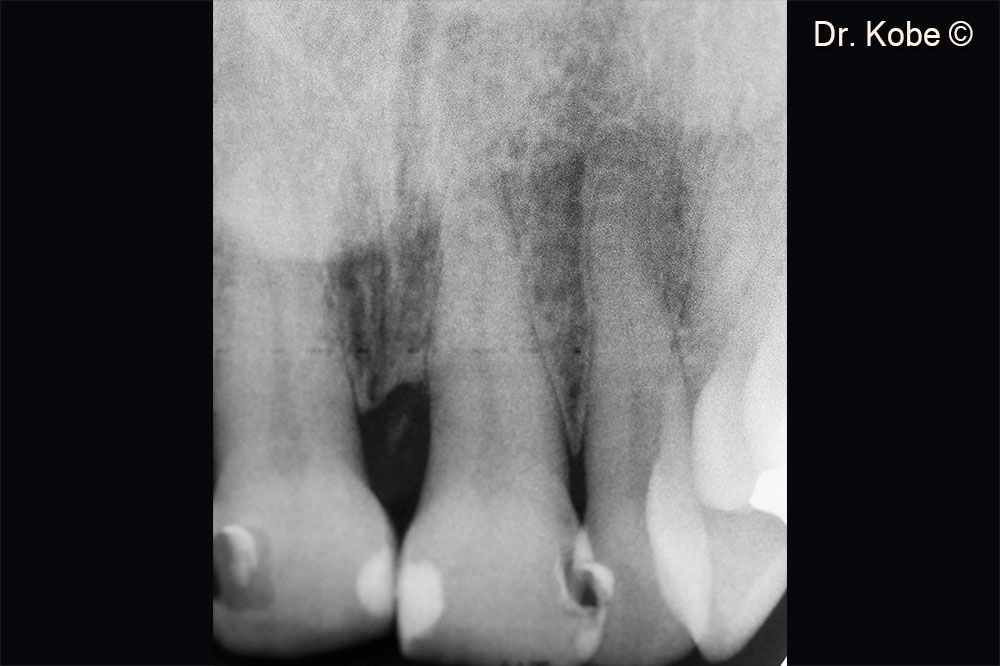

2. Vertical bone defect on the x-ray image

10. Initial x-ray